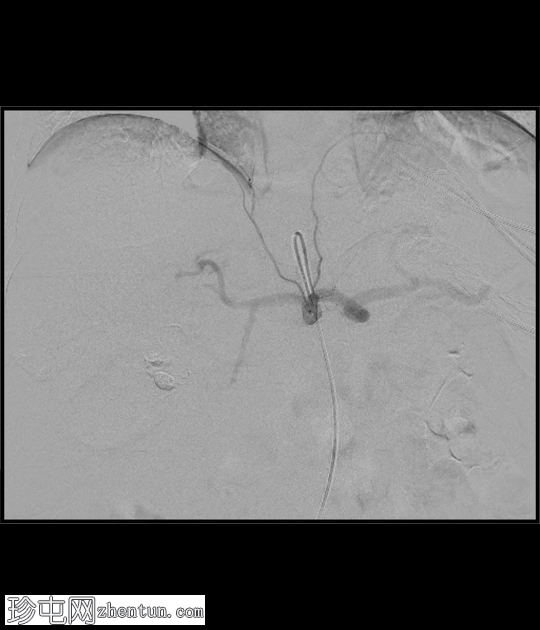

DSA

4.png

正面

腹腔干

血管造影证实存在胆囊动脉假性动脉瘤,并伴有活动性出血征象。

行胆囊动脉栓塞术,术后血管造影显示疗效满意。